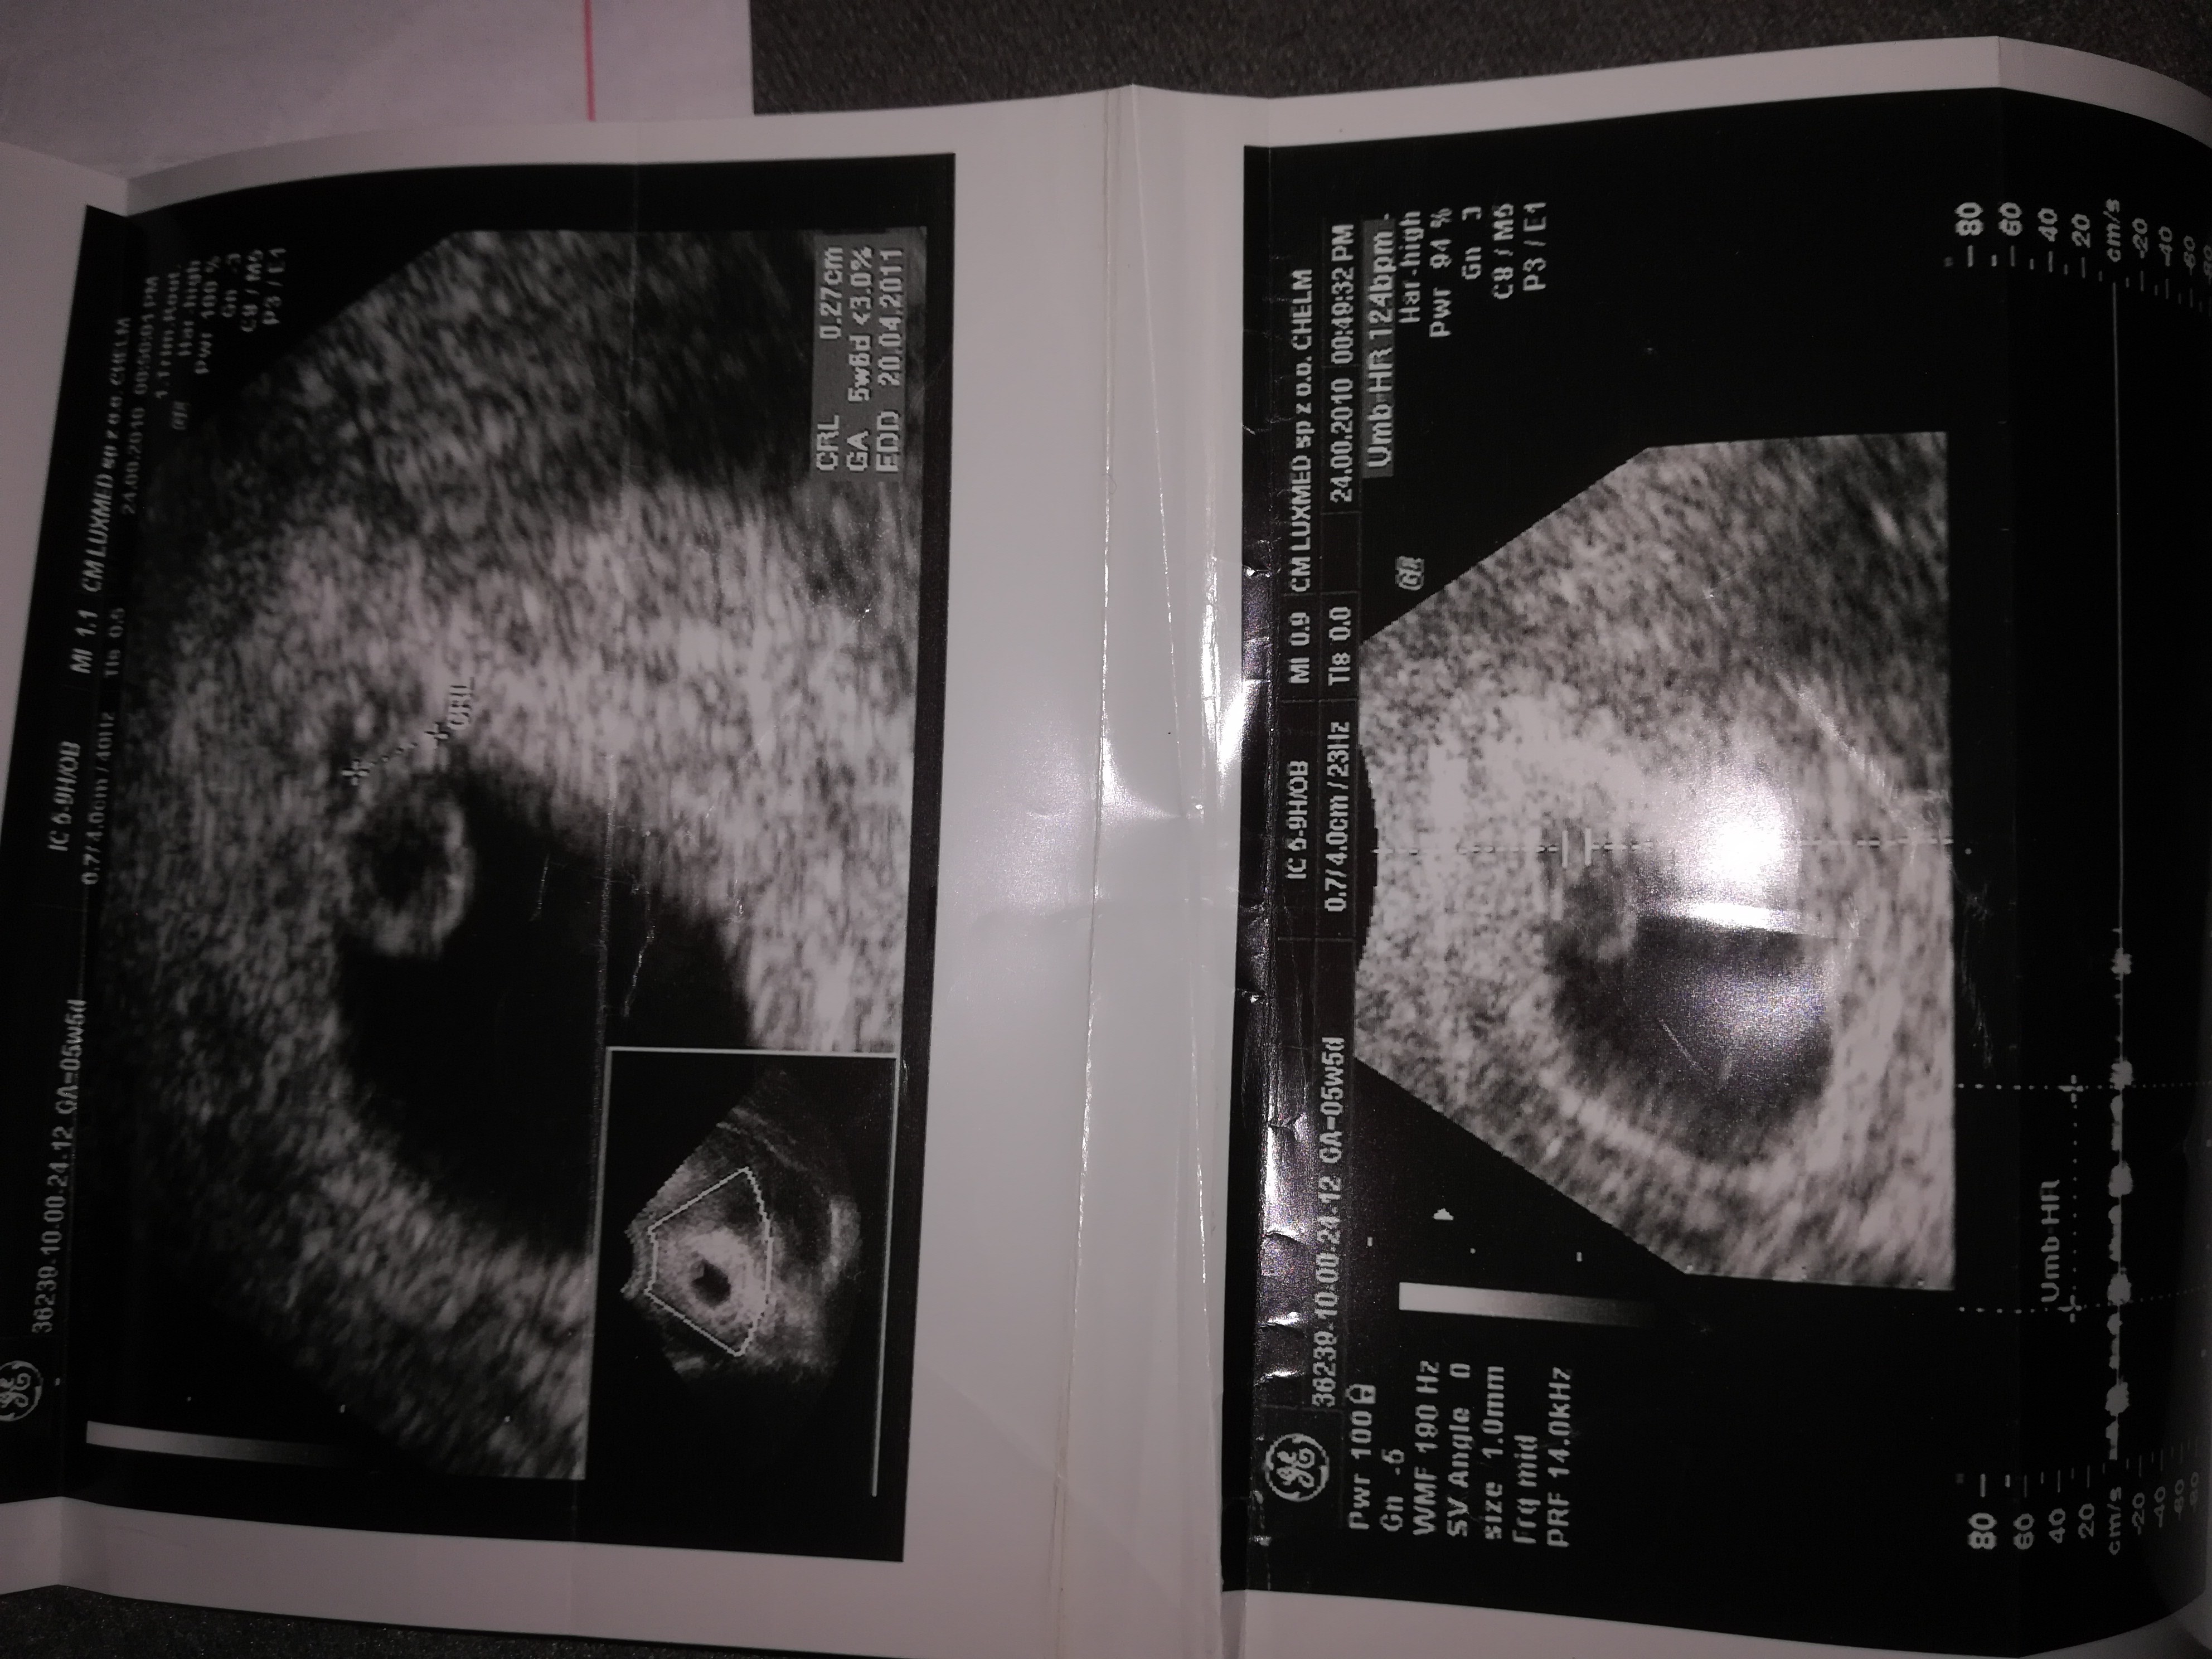

I w tym 5 tydzień 5 dzień mam zaznaczone że biło serduszko dlatego byłam zdziwiona jak poszłam na usg że nie było widać zarodka tylko pecherzyk.

Zobaczcie to usg córki z 5 tygodnia i 12 tygodnia i w tym 5 mam serduszko zaznaczone